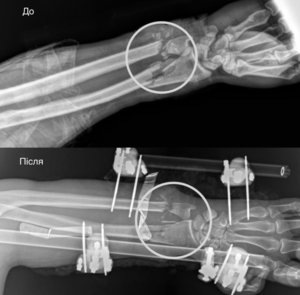

Медики зазначають, що травма була критичною: перерізані артерії, розтрощені кістки та пошкоджені нерви. Процес порятунку відбувався у кілька етапів:

- Ортопеди-травматологи стабілізували переломи за допомогою апарата зовнішньої фіксації.

- Судинні хірурги відновили кровопостачання, що стало вирішальним фактором для виживання тканин.